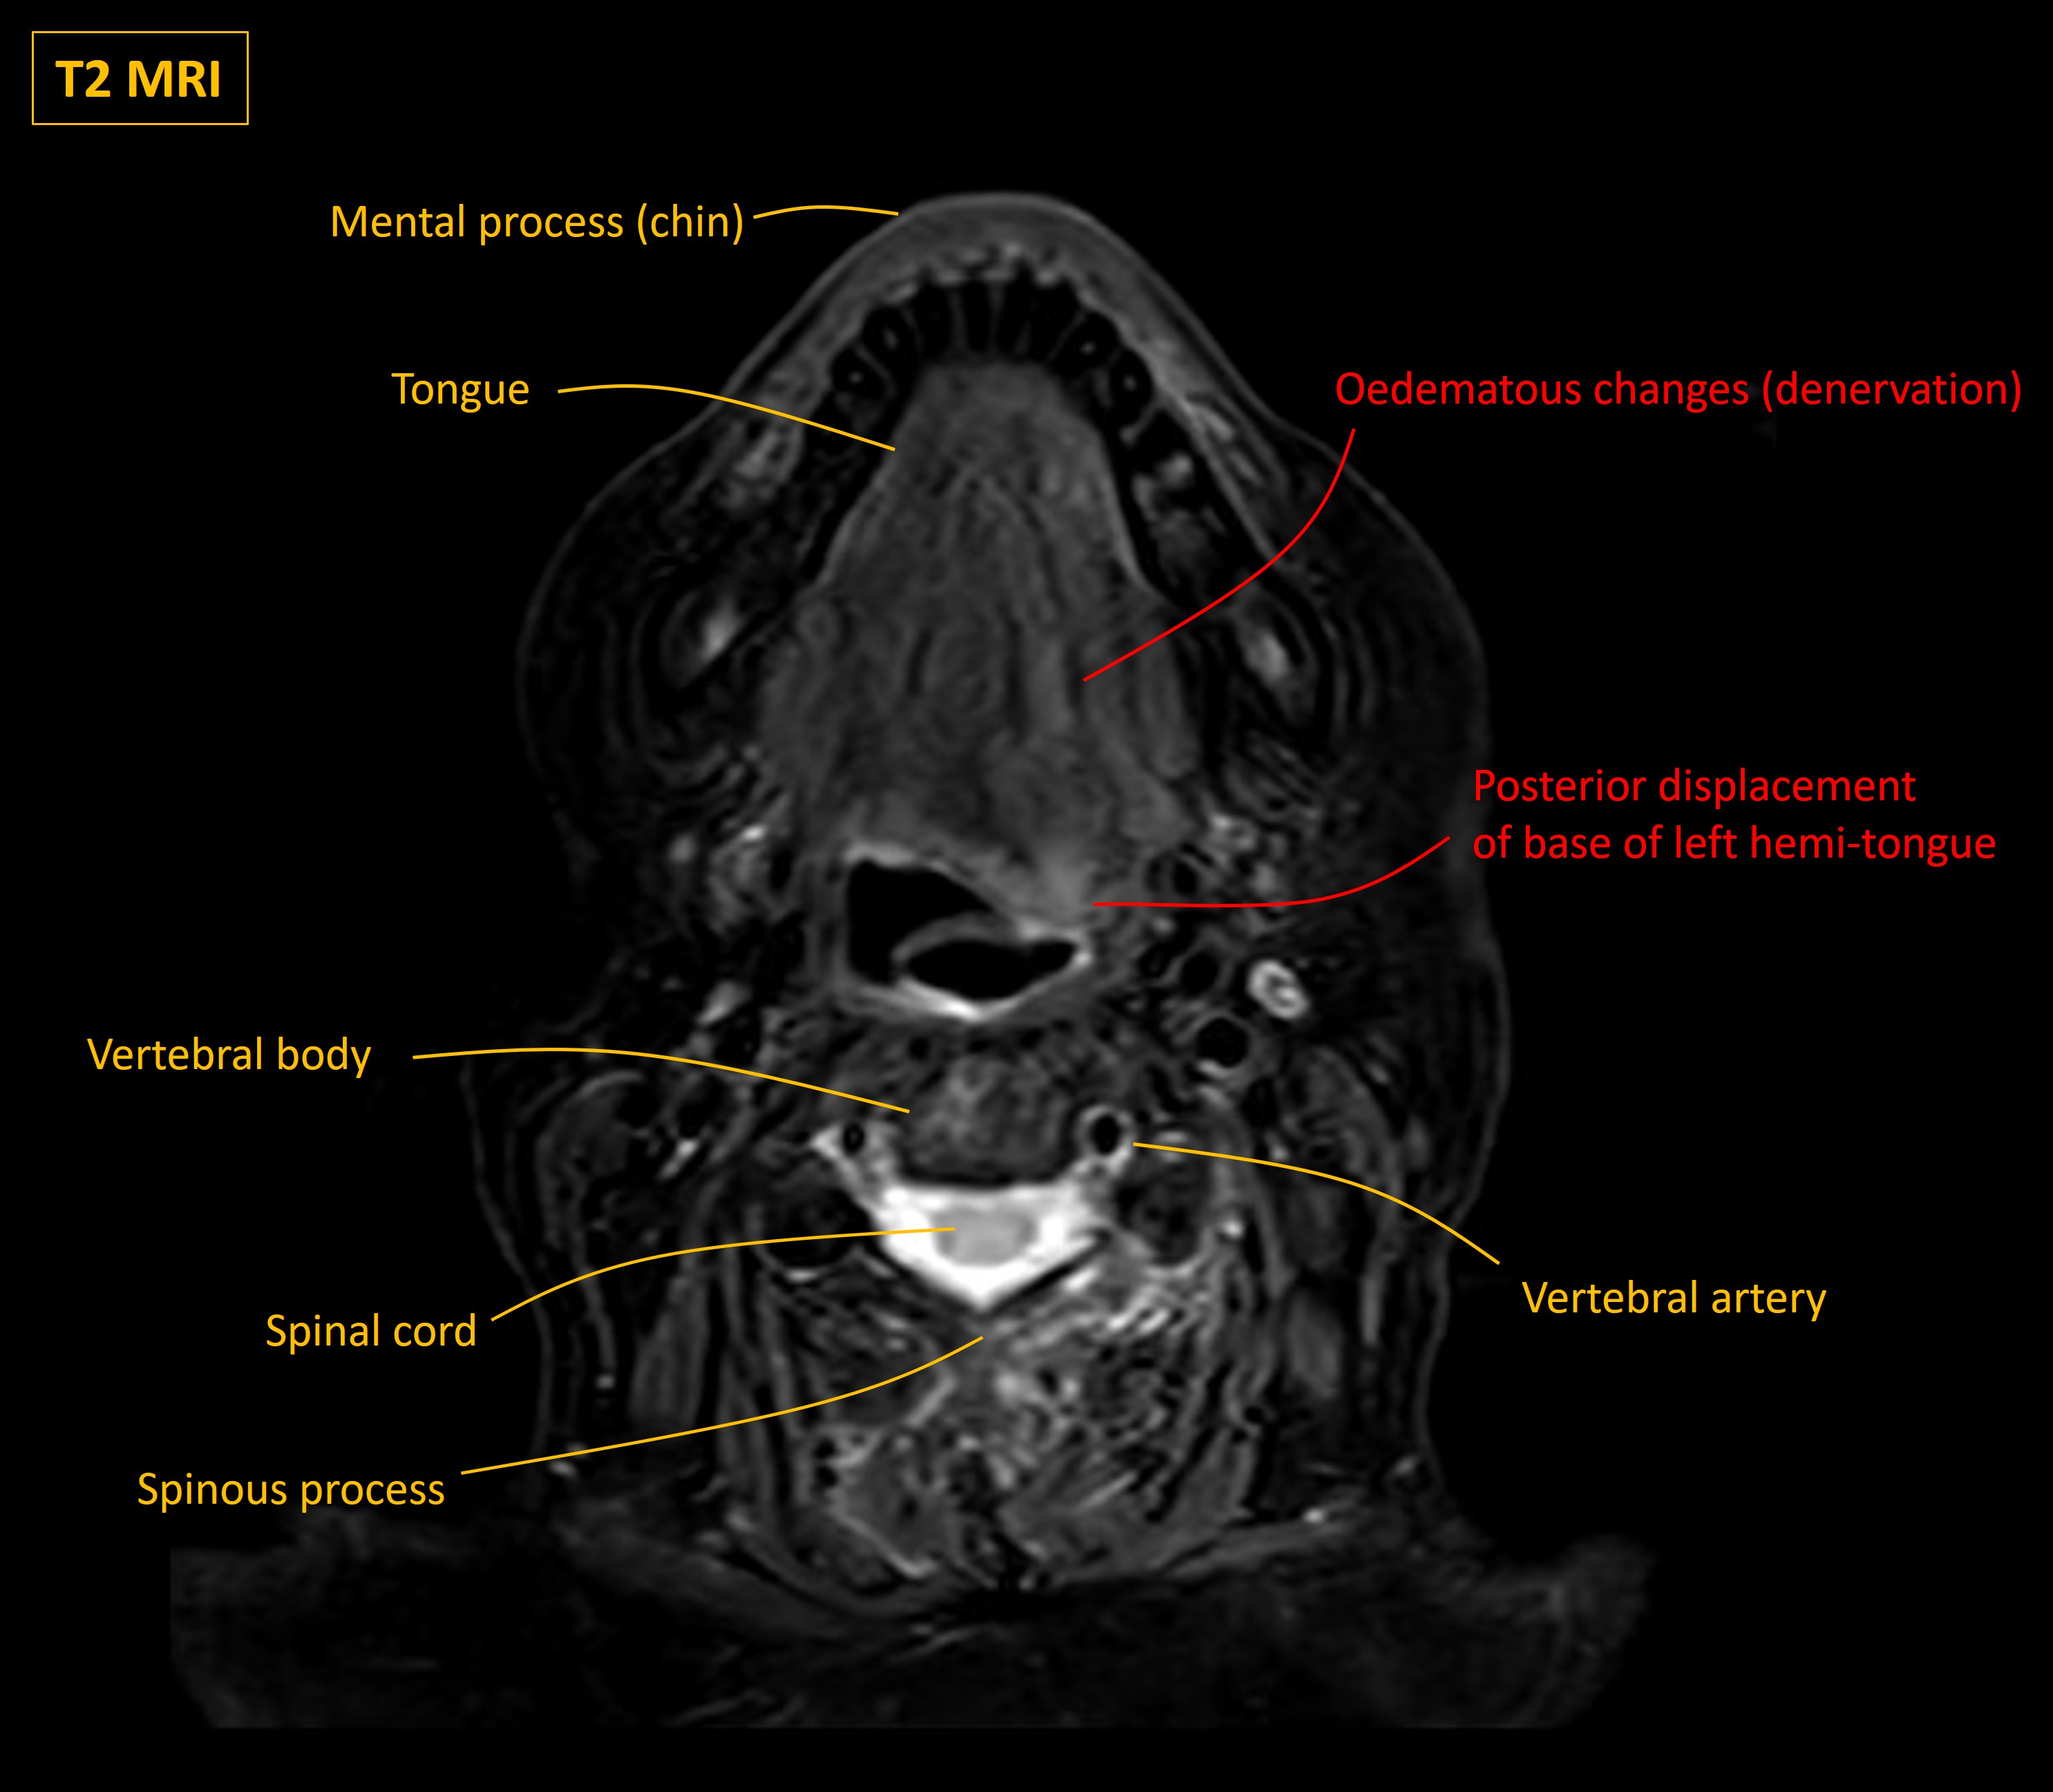

Urgent MRI head, skull base and neck were performed. These showed multiple bony metastases to the skull, including the skull base. A metastatic mass was invading the left occipital bone and affecting the hypoglossal canal, shown on the images below. The CT shows the key anatomy, and the MRI shows the mass:

The left half of the tongue was visibly bright on T2 MRI, indicating oedema due to denervation, and the base was posteriorly displaced due to weakness.